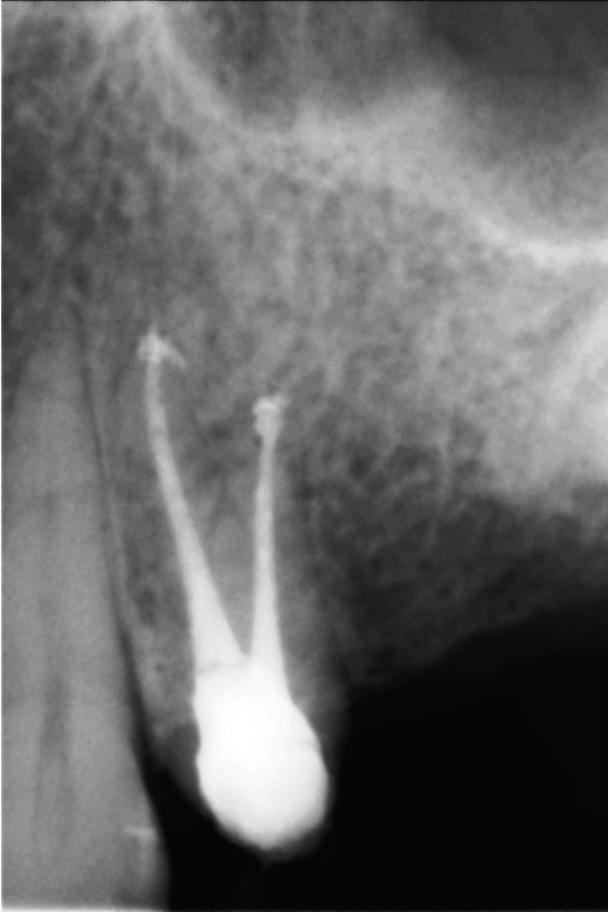

Полость корневых каналов промыли физиологическим раствором и восстановили зуб с помощью материалов для временного пломбирования. Чтобы предотвратить риск инфекции, в течение трех дней внутримышечно пациентке вводили клиндамицин (600 мг дважды в день), и также назначили ибупрофен (400 мг) для купирования боли, который она принимали по мере необходимости. Экстренное наружное использование холодных компрессов в первый день сменили на теплые компрессы во второй день для лечения отека. На первом повторном визите отмечалось увеличение кровоподтека, хотя припухлость значительно уменьшилась (фото 3). Отек и кровоподтек постепенно исчезали в течение всего периода наблюдения, а на 10 день после процедуры у пациентки исчезли все беспокоившие ее симптомы (фото 4). Для оценки соотношения между зубом, альвеолярным отростком и верхнечелюстной пазухой была проведена дентальная объемная томография (dental volumetric tomography — DVT) (NewTom 3G, QR SRL, Верона, Италия). На DVT-изображении было обнаружено, что апекс щечного корня перфорирует кортикальную пластинку верхнечелюстной кости, создавая, таким образом, свободный путь для проникновения ирригационного раствора в мягкие ткани (фото 5 (а) и фото 5 (б)). Через 10 дней симптомы полностью исчезли. В то же время в корневой канал наложили повязку с гидроксидом кальция. Во время заключительного посещения примерно через 4 недели после предыдущей процедуры корневые каналы запломбировали материалом AH Plus (Dentsply Maillefer) и гуттаперчей (фото 6).

Фото 6: Рентгенограмма приблизительно через 4 недели после пломбирования корневых каналов.